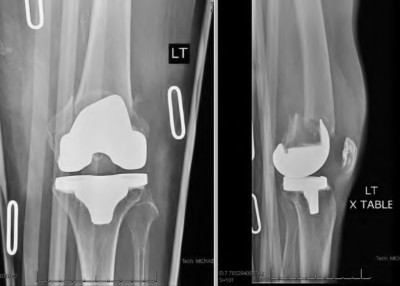

During a revision total knee arthroplasty, removal of the tibial component reveals a massive contained metaphyseal defect measuring 3 cm deep, but with an intact cortical rim. According to the Anderson Orthopaedic Research Institute (AORI) classification, what type of defect is this, and what is the preferred method of management?